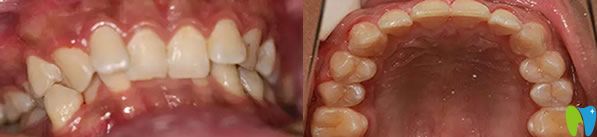

金屬托槽牙齒矯正前:

福州登特口腔牙齒矯正前

恒牙長上來后就開始擁擠不齊,門牙凹陷,虎牙前突,張嘴笑的時(shí)候總能看見牙齦外露,嘟個(gè)老婆嘴,下前牙輕度擁擠,因?yàn)樯涎赖脑?,?dǎo)致下牙也是內(nèi)凹,吃飯的時(shí)候感覺總是咬不住食物,咀嚼功能特別差。

來到福州登特口腔接診的是華醫(yī)生,經(jīng)過口腔檢查和分析,他建議我做金屬托槽牙齒矯正,不但經(jīng)濟(jì)實(shí)惠而且矯正效果好,這么好的有利條件我當(dāng)然毫不猶豫選擇了金屬托槽矯正。